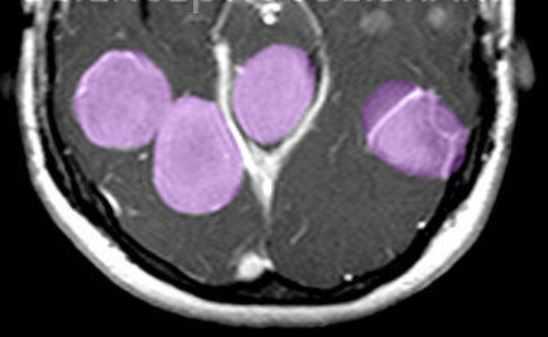

Туберозный склероз. Субэпендимальные узлы. Аксиальная Т-зависимая МРТ.

Субэпендимальные, то есть проецирующиеся в желудочек, но растущие со стороны паренхимы мозга, узлы чаще расположены рядом с хвостатым ядром или гипоталамической бороздой сразу за отверстием Монро, реже в области III, IV желудочков и Сильвиева водопровода. На Т2-взвешенных томограммах субэпендимальные узлы умеренно гиперинтенсивны и часто содержат кальцинаты . От астроцитом их отличает не столь яркий сигнал и меньшие размеры. Контрастирование при введении препаратов гадолиния иногда наблюдается и в субэпендимальных узлах , и всегда в астроцитомах.

Туберозный склероз. Гамартомы. КТ, Т2-зависимая МРТ и FLAIR

Туберозный склероз (синдром Бурневиля) встречается реже нейрофиброматоза. Его частота по данным литературы составляет около одного на 180 тыс. населения. От 20 до 40% случаев туберозного склероза унаследованы по аутосомно- доминантному типу, остальные возникли вследствии мутаций предположительно 9 и 11 пар хромосом (тип 1), либо 19 пары (тип 2). Поражение может затрагивать практически любые органы. Патогномоничными поражениями ЦНС являются корковые узлы в головном мозге и множественные субэпендимальные глиальные узлы , а также внутрижелудочковая гигантоклеточная астроцитома, встречаются сопутствующие аномалии - агенезия мозолистого тела, пахигирия, аневризмы. Характерны дерматологические проявления в виде множественных ангиофибром лица в форме «бабочки», бледные пятна на лице и груди, фибромы кожи, под ногтями и сетчатке глаза. Из других проявлений встречаются множественные ангиолипомы почек и печени, рабдомиомы сердца, лимфангиоматоз лёгких, костные склеротические и кистозные изменения. Диагноз туберозного склероза ставится при наличии у пациента 2 из перечисленных характерных признаков.

Корковые узлы - самое частое проявление туберозного склероза. Они расположены в коре головного мозга, деформируют её, захватывают прилегающее белое вещество и подвергаются кальцификации . При МРТ узлы изоинтенсивны серому веществу на Т1-взвешенных МРТ и чуть гиперинтенсивнее его на Т2-взвешенных. Контрастирование наблюдается в 5% случаев. В белом веществе обнаруживаются тяжи , отходящие радиально от желудочков. Корковые узлы и тяжи нередко называют «гамартомами», хотя они представляют собой скорее демиелинизацию и кальцификацию, чем истинную гетеротопию.